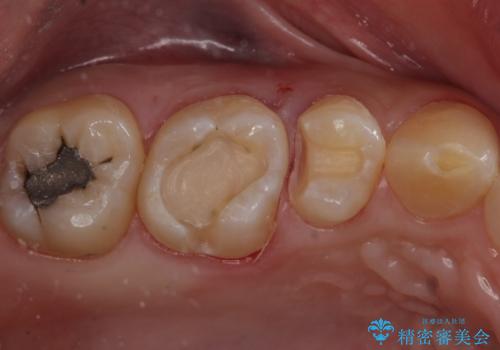

たまにしみる奥歯 セラミックインレーでの修復

- 奥歯がしみるとのことで来院。

検査の結果、明らかに虫歯がある歯と修復物との間に虫歯がある歯が確認されました。

2歯とも白くて適合の良いセラミックインレーでの修復をすることとなりました。